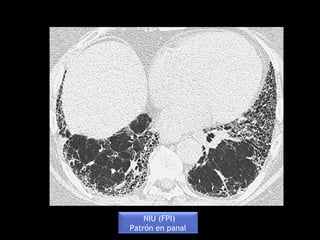

NIU (FPI)

Patrón en panal